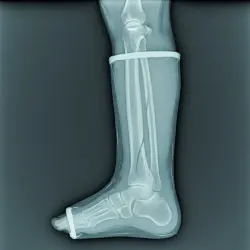

نمای چیدمان آموزشی عرض‌ها و طول‌های مختلف باند فایبرگلاس برای انتخاب سریع و دقیق

راهنمای انتخاب عرض و طول رول باند فایبرگلاس (Size Chart)

جدول سایزبندی باند فایبرگلاس: انتخاب عرض‌ ۵/۷.۵/۱۰/۱۲.۵ سانتی‌متر و طول رول ۳.۶–۴.۶ متر با قواعد هم‌پوشانی ۳۰–۵۰٪؛ پیشنهاد برای اطفال/بزرگسال، اندام فوقانی/تحتانی و اقلیم گرم‌مرطوب؛ برآورد تعداد رول.